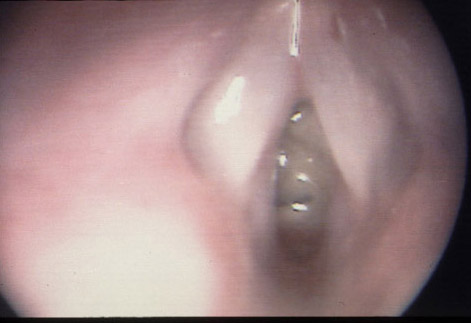

Endoscopic view showing a pecan nut wedged in the subglottis.